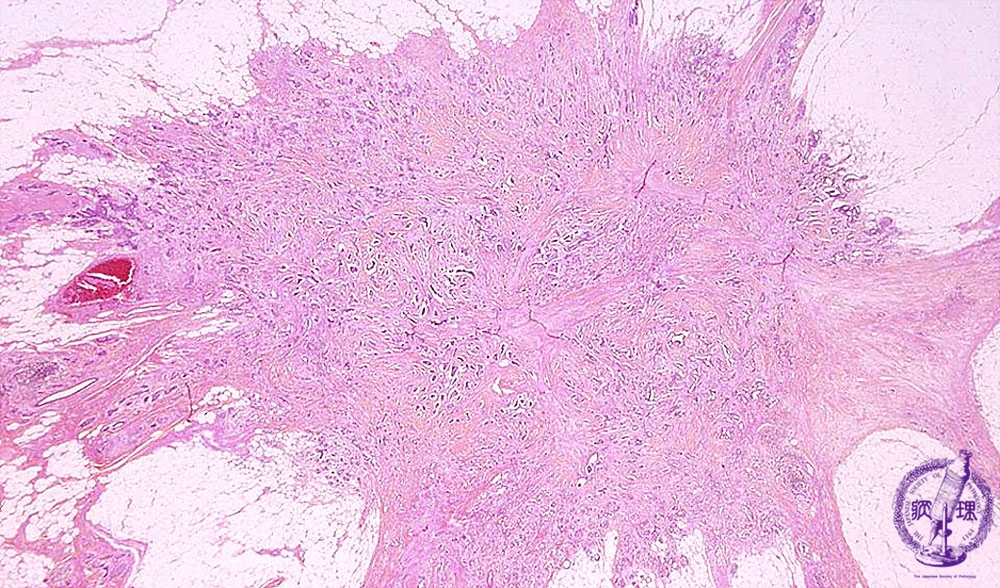

- ★(6)Invasive ductal carcinoma(Scirrhous carcinoma)

Microscopic image(HE stain, low power view):Tumor margin irregular with fluffing, representing the infiltration to adjacent adipose tissue.